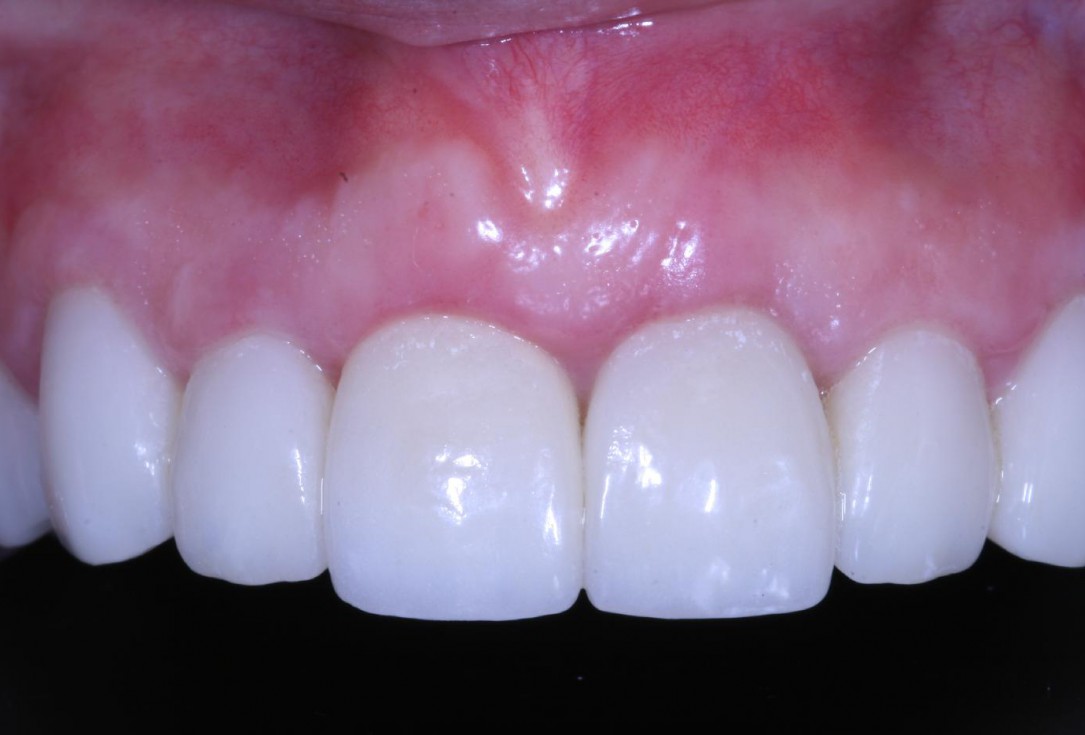

Longitudinal fracture on the root resected tooth 21 with visible buccal fistula